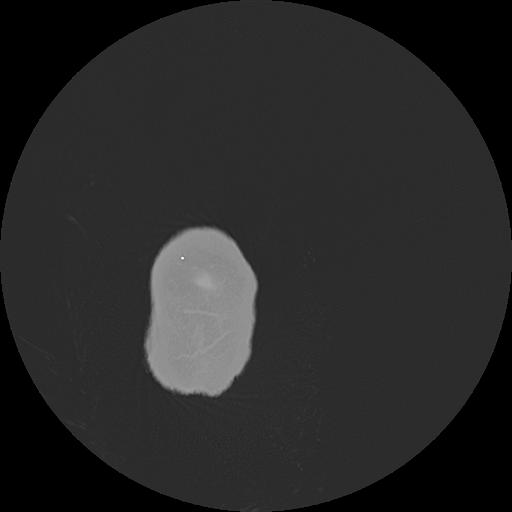

7 HUESO,,Vol,0.5,HUESO,,